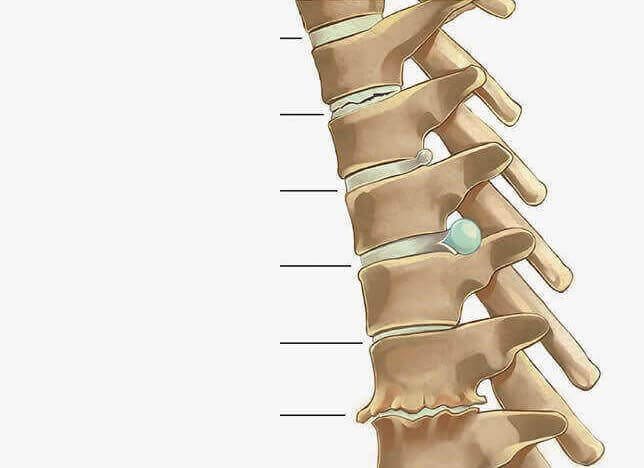

Disc articular normal

Modificări degenerative ale discului articular

Protruziunea discului

Alunecarea discului

Rafinarea discului

Degenerarea discului cu osteofită